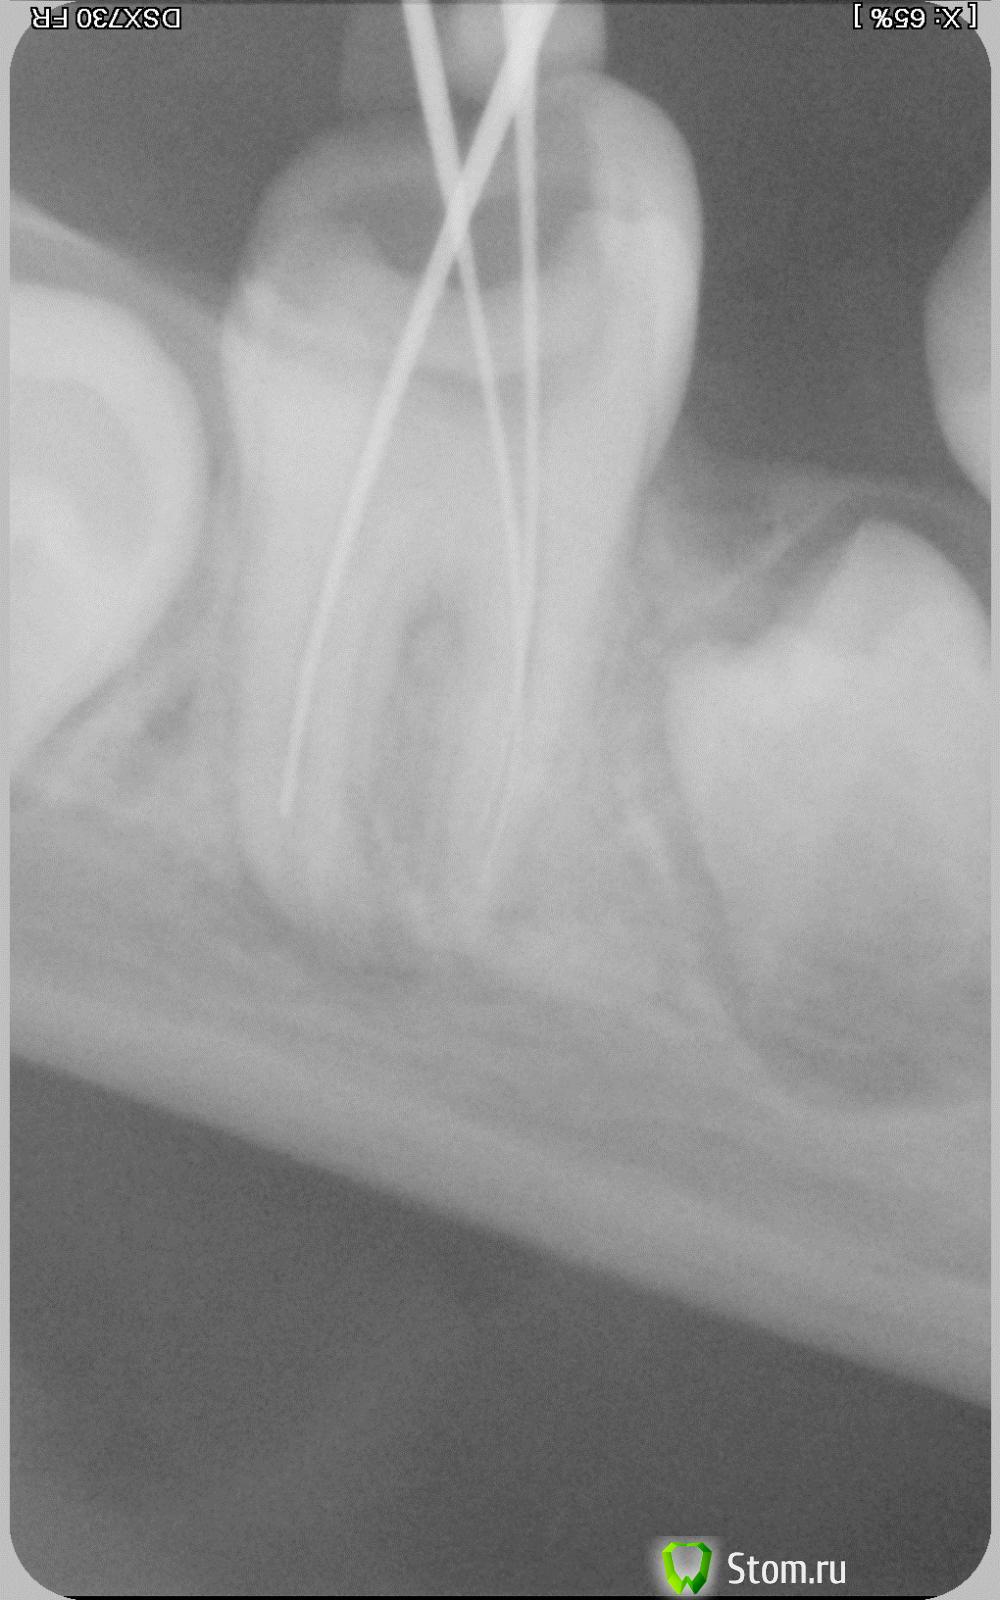

Rat84 Опубликовано 7 апреля, 2012 Поделиться Опубликовано 7 апреля, 2012 Здравствуйте, столкнулся с такой проблемой: пациентка, 9 лет. Месяц назад первый раз пришла на прием с диагнозом острый периодонтит 46. Зуб имел подвижность первой степени, огромную кариозную полость. Сделал снимок, удалил остатки корневой пульпы, расширил каналы и оставил зуб открытым. Удалил оставшийся корень молочного зуба, рядом с причинным. Со слов родителей - боль осталась на прежнем уровне после лечения (хотели ночью поехать и удалить - но не решились). Завтра, на повторном приеме еще раз обработал каналы, провел м/о и оставил ватку с жидкостью эндометазона на устье + временная пломба. Через часов 6 боль прошла, остался лишь дискомфорт при накусывании. Лечение продолжил через пару дней. Еще раз установил файлы, сделал контрольный снимок и запломибровал материалом Calasept. Через 5 дней повторил. Далее - через 7 и 14 дней. В данный момент зуб не беспокоит. При попытке ввести инструмент на всю длину корня (особенно дистального) - резкая боль даже после применения анестетика. В чем проблема, каким постоянным материалом пломбировать и когда, ну или одним вопросом - что делать дальше?Снимки сделаны с периодом в 1 месяц. Ссылка на комментарий

ннэт Опубликовано 9 апреля, 2012 Поделиться Опубликовано 9 апреля, 2012 На мой взгляд очень близко нижнечелюстной канал!!! В каком состоянии была пульпа при первичном обращении? Снимки тоже качественно не просматриваются. но корни сформированы. Причина болевой чувствительности может быть либо в том что выходите за широкий апекс прямо в н/ч канал, или в том что не доубрали гангренозную пульпу. Используйте доп методы анестезии + показания аплока Ссылка на комментарий

Джима Опубликовано 15 апреля, 2012 Поделиться Опубликовано 15 апреля, 2012 наконец-то с компа захожу и вижу снимки. +1 к нижнечелюстному каналу и плохому качеству снимков. но мне кажется, верхушки всё же не закрыты, дистальный так точно. Ссылка на комментарий

Паращук Роман Опубликовано 22 апреля, 2012 Поделиться Опубликовано 22 апреля, 2012 Рентгенограммы не удов. Рен-мма-это срез в одной плоскости. Думаю до канала н\ч как до Китая. Имеется остаточный пульпит и неадекватное обезболивание. По тому что видел,работайте с зубом как после зав-нной апексофикации. Если не удастся сделать апикальный упор на уровне макс 40-го разм. ,мта в апикальную часть+ ваш метод обтурации к\к. Ссылка на комментарий